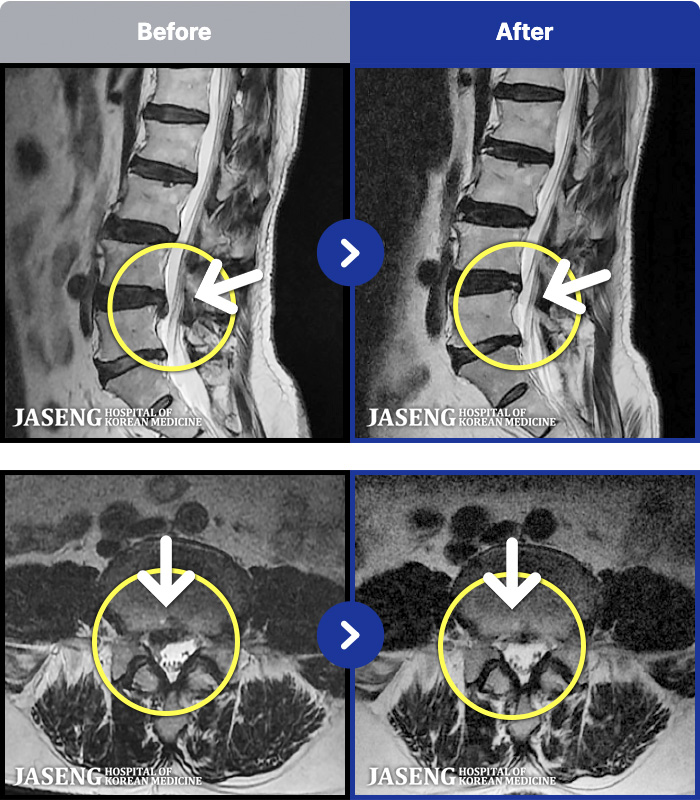

1,237 MRI ũ ʸ Ȯϼ.

1,237